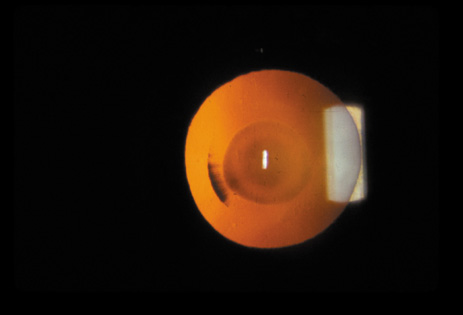

The PSC is the least prevalent subtype in most population-based studies.18 These cataracts often occur in combination with nuclear or cortical cataracts in the later stages. They are easily noticed on retroillumination because they are usually located centrally, and may interfere with funduscopy (Fig. 12). In early stages, patients usually complain of subjective symptoms such as glare disability32 and difficulty focusing on near objects. This is because when the pupil constricts during accommodation, the light entering the eye becomes concentrated centrally, where the PSC is also located. This causes light scattering and interferes with the ability of the eye to focus an image on the macula. In addition, these opacities lie at or near the nodal point of the eye, further interfering with focusing of the image on the macula.

Fig. 12. PSC. Note the central location, which gives rise to severe glare disability.